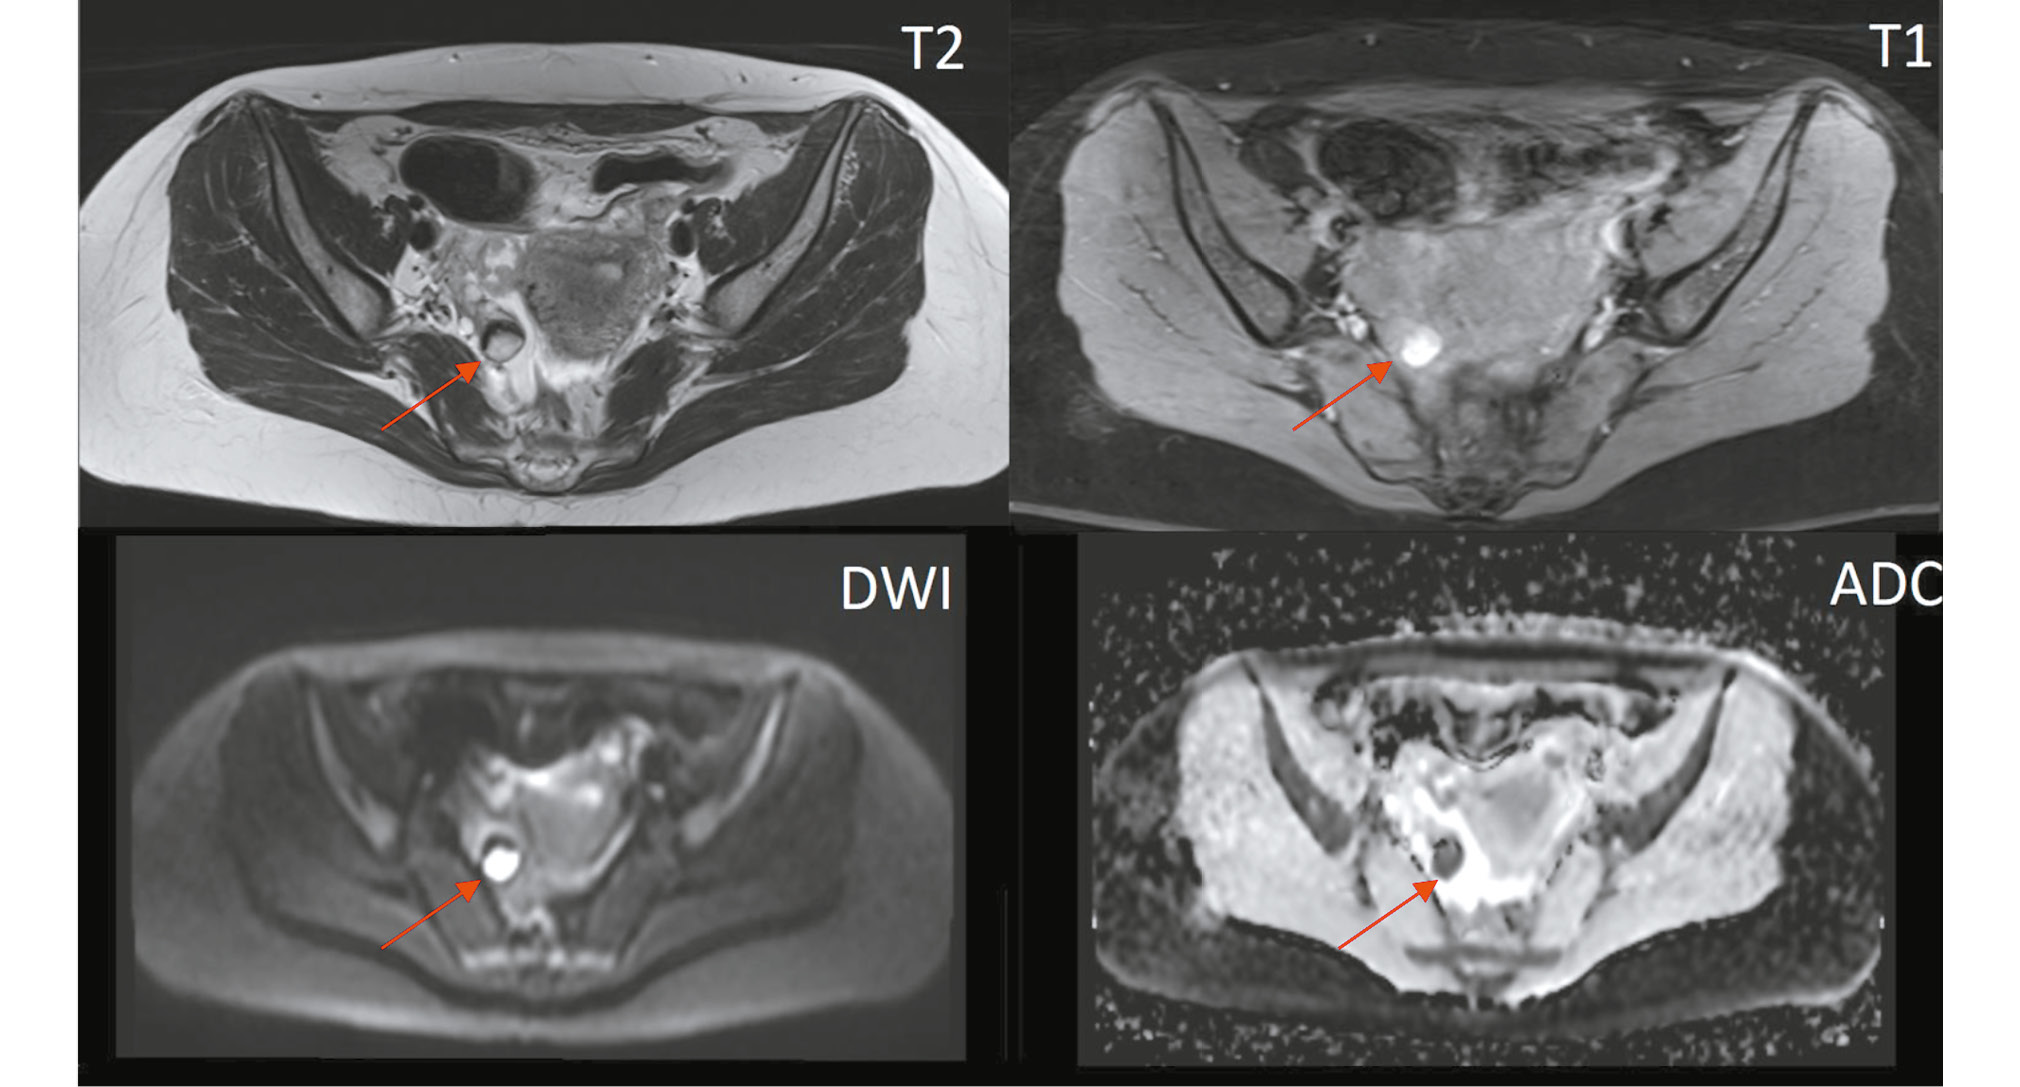

MRI results showed that the ovaries were not enlarged and contained follicles; a hemorrhagic cyst was identified in the right ovary (Figs. 2 and 3).

Fig. 2. Pelvic magnetic resonance imaging (axial view). A single hemorrhagic cyst is observed in the stroma of the right ovary (O-RADS 1, red arrow).

Fig. 3. Pelvic magnetic resonance imaging (axial view). The left ovary shows follicles and a simple cyst (O-RADS 1, red arrow).